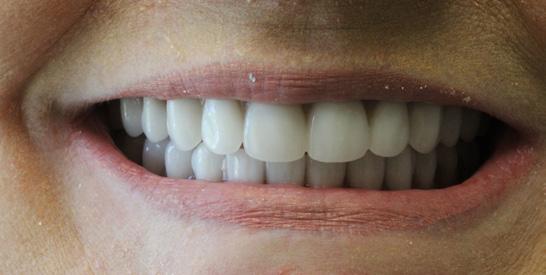

New Teeth In One Day, A state-of-the-art technique performed by Dr. Gregory

Do you ever catch yourself missing the familiar comfort of your own teeth? Frustrated with dentures that just don’t look or feel right? Or maybe, the mere thought of dentures has kept you from seeking treatment, fearing a life without the authenticity of your natural smile?

Welcome to Dr. Gregory’s “Teeth In One Day” solution – a transformative experience tailored just for you. This isn’t about just replacing teeth; it’s about reviving the confidence of your natural smile.

Imagine walking into Dr. Gregory’s cozy office, where you’re gently sedated for a worry-free procedure. Once you’re comfortably at ease, we replace any existing teeth with 4 to 6 state-of-the-art dental implants, precisely set into your jawbone. But here’s where the magic truly happens: a set of teeth, custom-

crafted uniquely for you, is secured onto these implants. This isn’t a temporary fix. These teeth will not only look, feel, and function like your natural teeth, but they’ll also stay with you, day in and day out – no nightly removals, no adjustments. Simply a new, permanent smile that’s unmistakably yours.

Why choose Dr. Gregory’s Teeth In One Day?

Commitment Beyond Procedures: We provide a lifetime of follow up care and personal accountability for our work. We won’t refer you out of our practice after your surgery is complete. We see you at least once a year to check our work and evaluate the health, function, and esthetic of your implants and your new teeth. You become part of our patient family.

Double the Care, Double the Quality: We provide you with two full sets of new teeth. Other practices frequently offer only one set of all-plastic (acrylic) teeth the day of surgery. We believe it is not acceptable to deliver an allplastic set of teeth as a final solution (plastic is porous and grows bacteria and fungus, is rough and difficult to clean). We provide an additional final set of teeth made of titanium with esthetic overlay or made of zirconia (ceramic). These materials are appropriate to protect the implants from infection and to provide a durable chewing solution and a beautiful long term result.

Unwavering Quality Standards: Your smile deserves the best. And we make no compromises there. We use quality implants and authentic implant parts. Dental implants are made by various manufacturers and are not all equal in quality or research support. Implants backed by years of research cost ten times what “knock off” implants can cost. Authentic parts that are fabricated to fit those implants are also more costly. We believe it’s absolutely worth the cost to have quality implants and implant parts used during surgery in an effort to minimize implant failures.

Tailored Just for You: No two smiles are the same, and neither should be the approach to care for them. We provide a customized surgery strategy for every patient. There is no one surgical plan that fits every patient. Every patient has a different dental history and a different personal story. There are many treatment options and we feel proud to offer a wide variety of techniques. We listen to our patients and help them arrive at a plan that makes sense for their dental condition, their emotional needs, and their financial possibilities.

Say goodbye to the inconveniences of conventional dentures and embrace a renewed, authentic smile with Dr. Gregor where you’re not just another patient; you’re family.

We offer comprehensive family dentistry and specialist services under one roof including preventive family dental cleanings, fillings, crowns, veneers, oral surgery, adult orthodontics, and periodontics. We also offer in-house dental insurance and work with employer insurance plans. We have a variety of financing options available.

Before & After Before & After